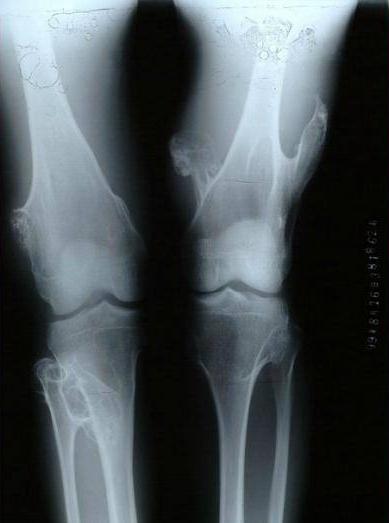

X线片可见近干骺端部位的骨性突起,基底部有时较宽,有时较窄,蒂部与骨干相连,髓腔彼此相通。突起的表面为软骨帽,不显影,所以肿瘤的实际大小可能要比x线平片上要大。和x线相比,CT和核磁共振对位于骨盆、肩胛骨和脊柱上的骨软骨瘤能够更清楚的显示软骨帽的范围及与周围软组织的关系,具有更好的显示效果。

男性多发,肿瘤分布广泛且相对对称。在全身任何存在软骨的骨骼中几乎都有可能发生。由于肿瘤多发,所以很难依据外科手段全部切除。多表现为全身多发的骨性包块,常伴有骨骼短缩和畸形,如膝、踝、肘、腕关节的内外翻畸形。影像学上和单发的骨软骨瘤基本相同,只是肿瘤数量上的不同及存在骨骼畸形而已。